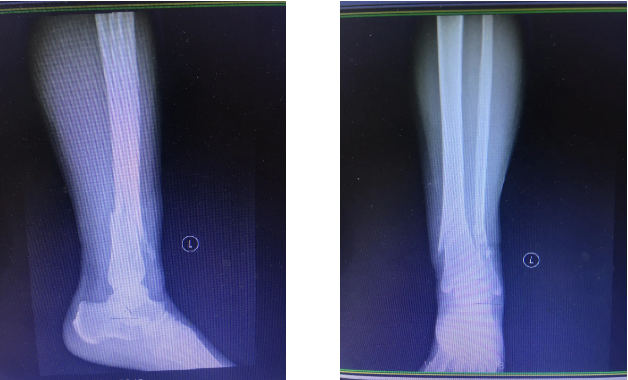

患者,女,54岁,因外伤后左踝部肿痛、活动受限3小时入院,入院后诊断为左胫腓骨远端骨折,入院后左侧小腿远端明显肿胀,畸形,压痛、叩痛明显,局部可见大量张力性水疱。骨一科王金台主任马上组织病例讨论,并制定详细周密的手术计划,同时在患者及家属知情同意后实施胫骨远端骨折逆行髓内钉内固定术+腓骨骨折髓内钉内固定术,手术顺利完成。手术切口小、创伤小,对骨折端的血运基本无破坏,术后拍片骨折复位固定良好。

手术前